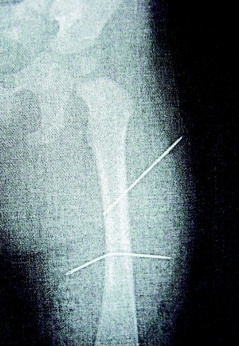

隔月27日,該女子又見外甥女哭鬧不停,拿蒼蠅拍朝著外甥女背部連打數十下,造成女娃背部瘀傷。經女娃母親發(fā)現后送醫(yī)救護,院方為女童進行X光片照射后,才發(fā)現女娃左大腿里竟有兩根縫衣針。